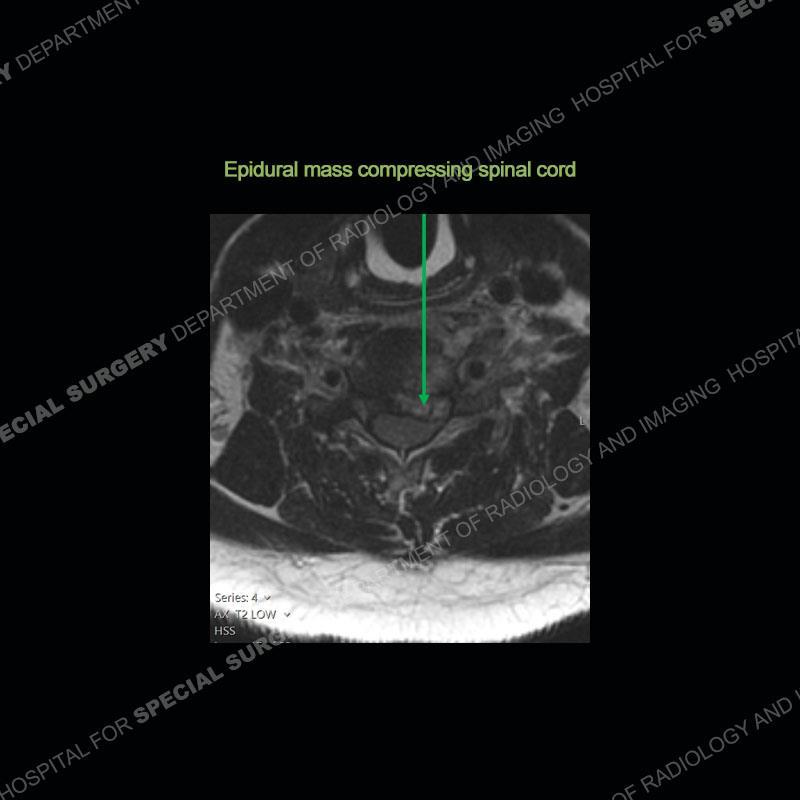

The radiographs demonstrate a prevertebral soft tissue fullness centered at C5-C6 that persists even on extension. There is a slight loss of disc height at C5-C6. The CT more readily shows the prevertebral soft tissue swelling at C5C6 where there is a punctate focus of gas. On the MRI, there is a marked amount of edema and a heterogeneous collection in the prevertebral soft tissue at C5-C6. Edema is present of the C5 and C6 vertebral bodies with a loss of the normal architecture about the disc space. A heterogeneous epidural collection has formed that causes compression of the spinal cord asymmetric to the left side and also precipitates severe left sided neural foraminal stenosis.